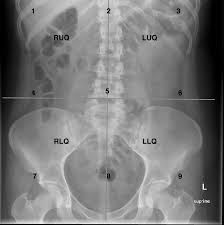

As you can see in the diagram, the four abdominal quadrants are located in the space directly below the diaphragm. The abdominal quadrants can create a differential diagnosis for the cause, along with ot Given an ordered pair of the form (x,y), y is called the adcissa c. The quadrants are referred to as the left lower quadrant, left upper quadrant, right upper quadrant and right lower quadrant. The division into four quadrants permits the localization of pain and tenderness or other discomforts.

Graph with the 4 quadrants labeled on a coordinate plane. The abdomen is anatomically divided by two horizontal lines and two vertical lines. What does abdominal quadrants mean? Abdominal quadrants labeled / bony thorax, chest, and abdomen | radiology key / divided into 9 regions by divided into 4 quadrants by single vertical and horizontal imaginary planes. Start studying cma abdominal quadrants label. Thank you for visiting picture of abdominal quadrants pictures. If you plan to enter a healthcare profession such as nursing, this is something you'll use on the job when performing abdominal assessments (and while documenting). Abdominal surface anatomy can be described when viewed from in front of the abdomen in 2 ways: Abdominal surface anatomy can be described when viewed from in front of the abdomen in 2 ways:. The quadrants are labeled by location: These regions and quadrants are of clinical importance when examining and describing pathologies related to the abdomen The organs contained in the abdominal cavity can be localized based on these four sections. The right upper, right lower, left upper, and left lower quadrants.

The quadrants are defined by drawing an imaginary line vertically (top to bottom) and horizontally (sideways) though the umbilicus (belly button). These regions and quadrants are of clinical importance when examining and describing pathologies related to the abdomen Abdominal_quadrants_cleaned_labeled.png ‎(615 × 598 pixels, file size: Since the abdominal area contains many different organs it is divided in smaller areas. Nine abdominal regions the upper horizontal line also called transpyloric line is midway between xiphisternum and umbilicus. The quadrants are referred to as the left lower quadrant, left upper. This will be useful if you plan to enter a healthcare. Abdominal quadrants are a way of sectioning internal organs into four regions for diagnostic, and descriptive purposes.

Start studying cma abdominal quadrants label. The quadrants are referred to as the left lower quadrant, left upper. Key points the abdominopelvic cavity can be subdivided into four quadrants and nine areas. The division into four quadrants allows the localisation of pain and tenderness, scars, lumps, and other items of interest, narrowing in on which organs and tissues may be involved. Need to improve your knowledge of abdominal anatomy? These regions are named by their location: The four quadrants of thecartesian coordinate system. This will be useful if you plan to enter a healthcare. Abdominal_quadrants_cleaned_labeled.png ‎(615 × 598 pixels, file size: Abdominal surface anatomy can be described when viewed from in front of the abdomen in 2 ways: The quadrants are labeled by location: The two horizontal lines are: This abdominal pain diagram and chart defines the meaning of stomach pain using quadrants.

Abdominal quadrants labeled / bony thorax, chest, and abdomen | radiology key / divided into 9 regions by divided into 4 quadrants by single vertical and horizontal imaginary planes. Quadrants labeled with pi : The division into four quadrants allows the localisation of pain and tenderness, scars, lumps, and other items of interest, narrowing in on which organs and tissues may be involved. Since the abdominal area contains many different organs it is divided in smaller areas. The human abdomen is divided into quadrants and regions by anatomists and physicians for the purposes of study, diagnosis, and treatment.